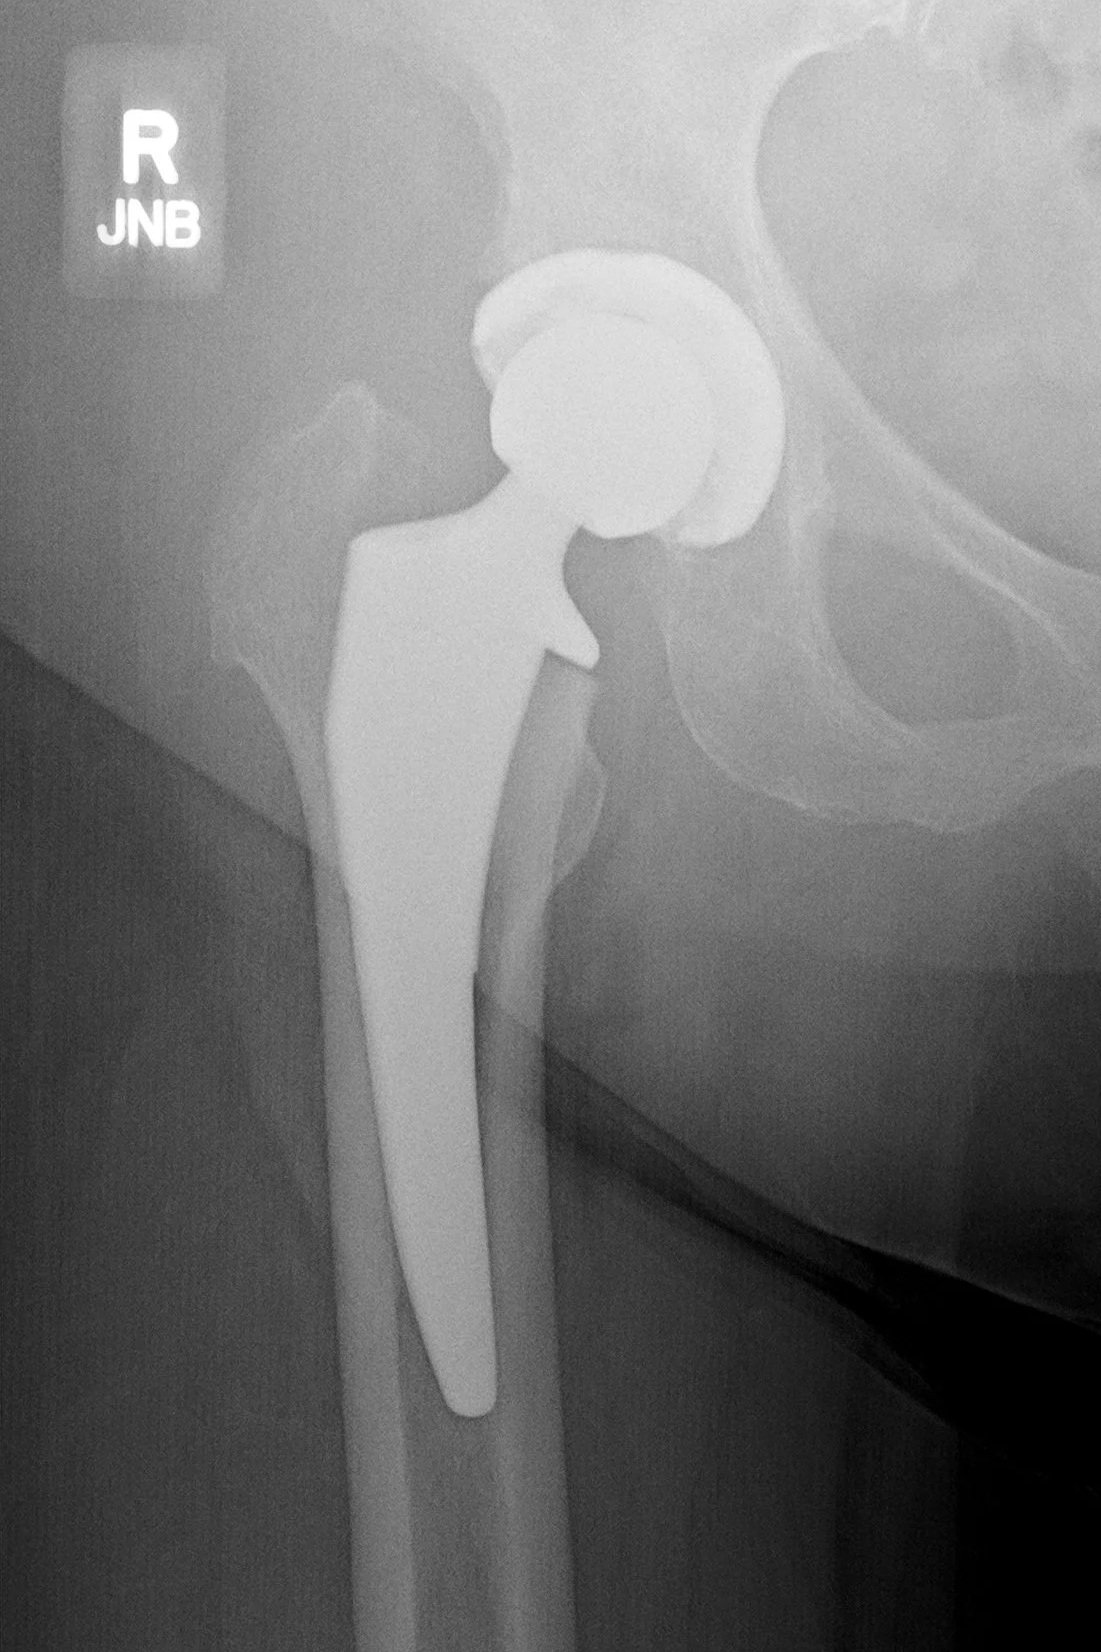

X-ray showing total hip replacement implant after anterior hip surgery.

After Surgery

Total hip replacement

After total hip replacement, the damaged joint surfaces are replaced with precision-positioned components. The acetabular cup and femoral stem restore alignment, stability, and joint mechanics.